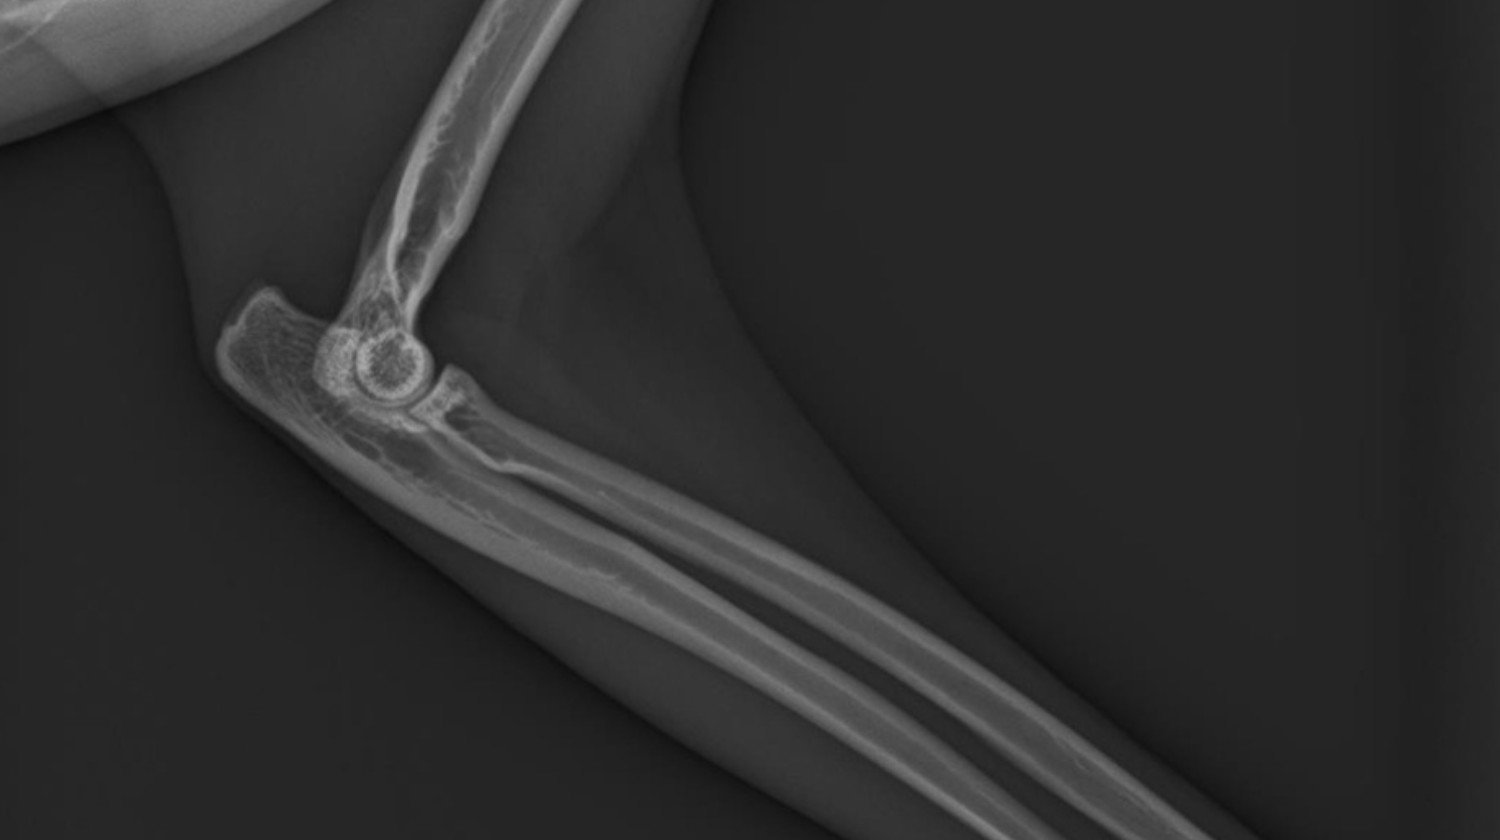

Notre famille vient de vivre une tragédie déchirante : notre chat bien-aimé a été renversé par une voiture. Sa patte est gravement cassée, elle souffre énormément et les vétérinaires disent que seule une intervention chirurgicale immédiate et salvatrice peut lui donner une chance de survivre. Chaque minute d'attente diminue ses chances.

Une immense tragédie est arrivée à notre famille : notre chat adoré a été renversé par une voiture. Dans l'accident, sa patte a été gravement cassée, il souffre énormément, et les vétérinaires disent que seule une chirurgie immédiate et salvatrice peut lui donner une chance de survie. Chaque minute d'attente diminue ses chances de survie.